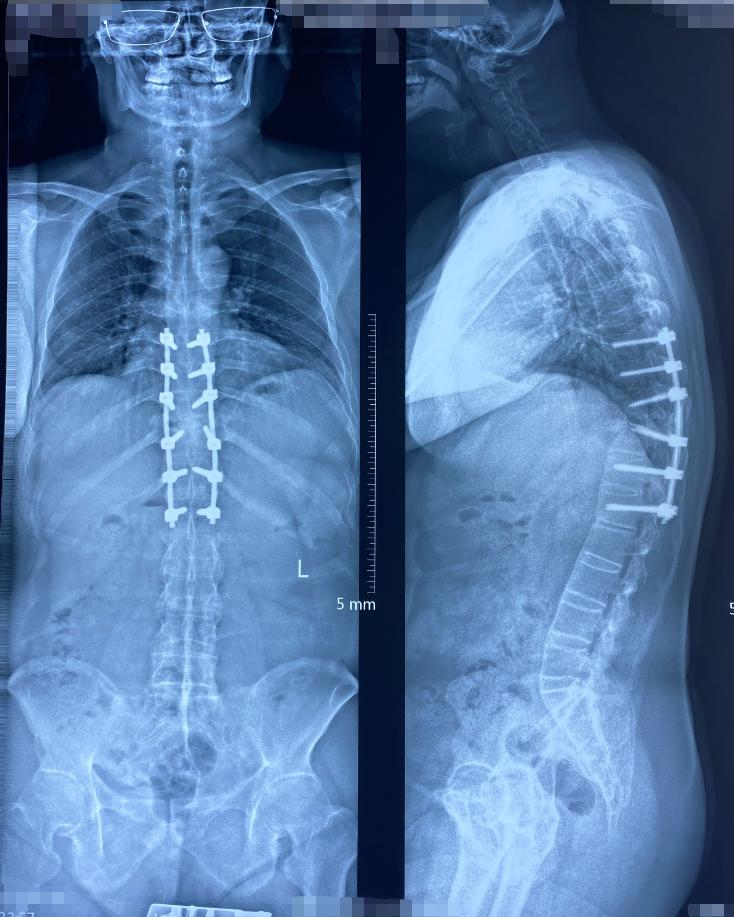

听了这些讲解后,吴先生更加坚定了手术的决心。于是我们为吴先生尽快进行了后路长节段的椎间植骨融合固定手术。手术圆满成功,重建了脊柱稳定性,并给受压的脊髓进行了彻底的减压。术后,吴先生的下肢症状立即得到了明显缓解。

前几天,吴先生过来进行他术后三年的复查,经过影像学检查片子上显示,他缺失的脊柱又重新长回来了!但是这次他又出现了新问题,怎么回事呢?

(骨质重新长出来了)